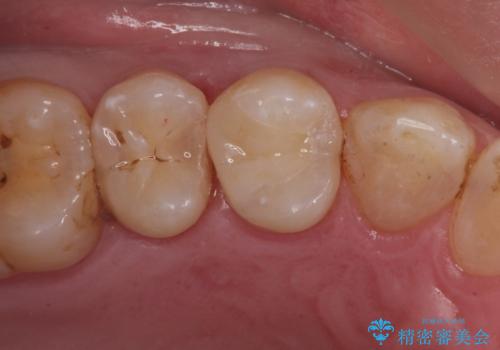

歯と歯の間の虫歯(コンタクトカリエス)

レントゲンで歯と歯の間に虫歯(コンタクトカリエス)があったので

拡大鏡下で虫歯を全て除去して、e-maxインレーにて治療しました。

- e-maxインレー 7.7万円 費用は治療当時の料金となります